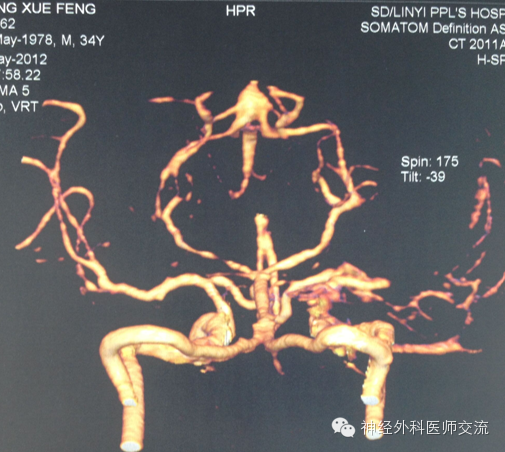

(2)CT图片处理——穿刺点的选择及介入手术入路

① 确定穿刺平面:据CT所显示的血肿,选择血肿最大断层,即为要穿刺的平面,也就是说:操作时要将引流导管沿着这一血肿最大层面进入血肿腔内。确定该层面至颅底层面的距离(即厚度)(X毫米:一般为50~60 mm)。

② 确定穿刺点:在血肿的最大层面上划出血肿的最大长轴线,与前额头皮的交点即为理论穿刺点,测出该点至血肿远端的距离(毫米),该数值减去5mm~10mm即为置管深度,一般为80~120mm。

确定实际穿刺点要做到两个避开:避开额窦、避开上矢状窦!实际穿刺点,一般为正中矢状线旁开15mm~20mm,内眦上方45mm~60mm的前额之交点,多为55mm。